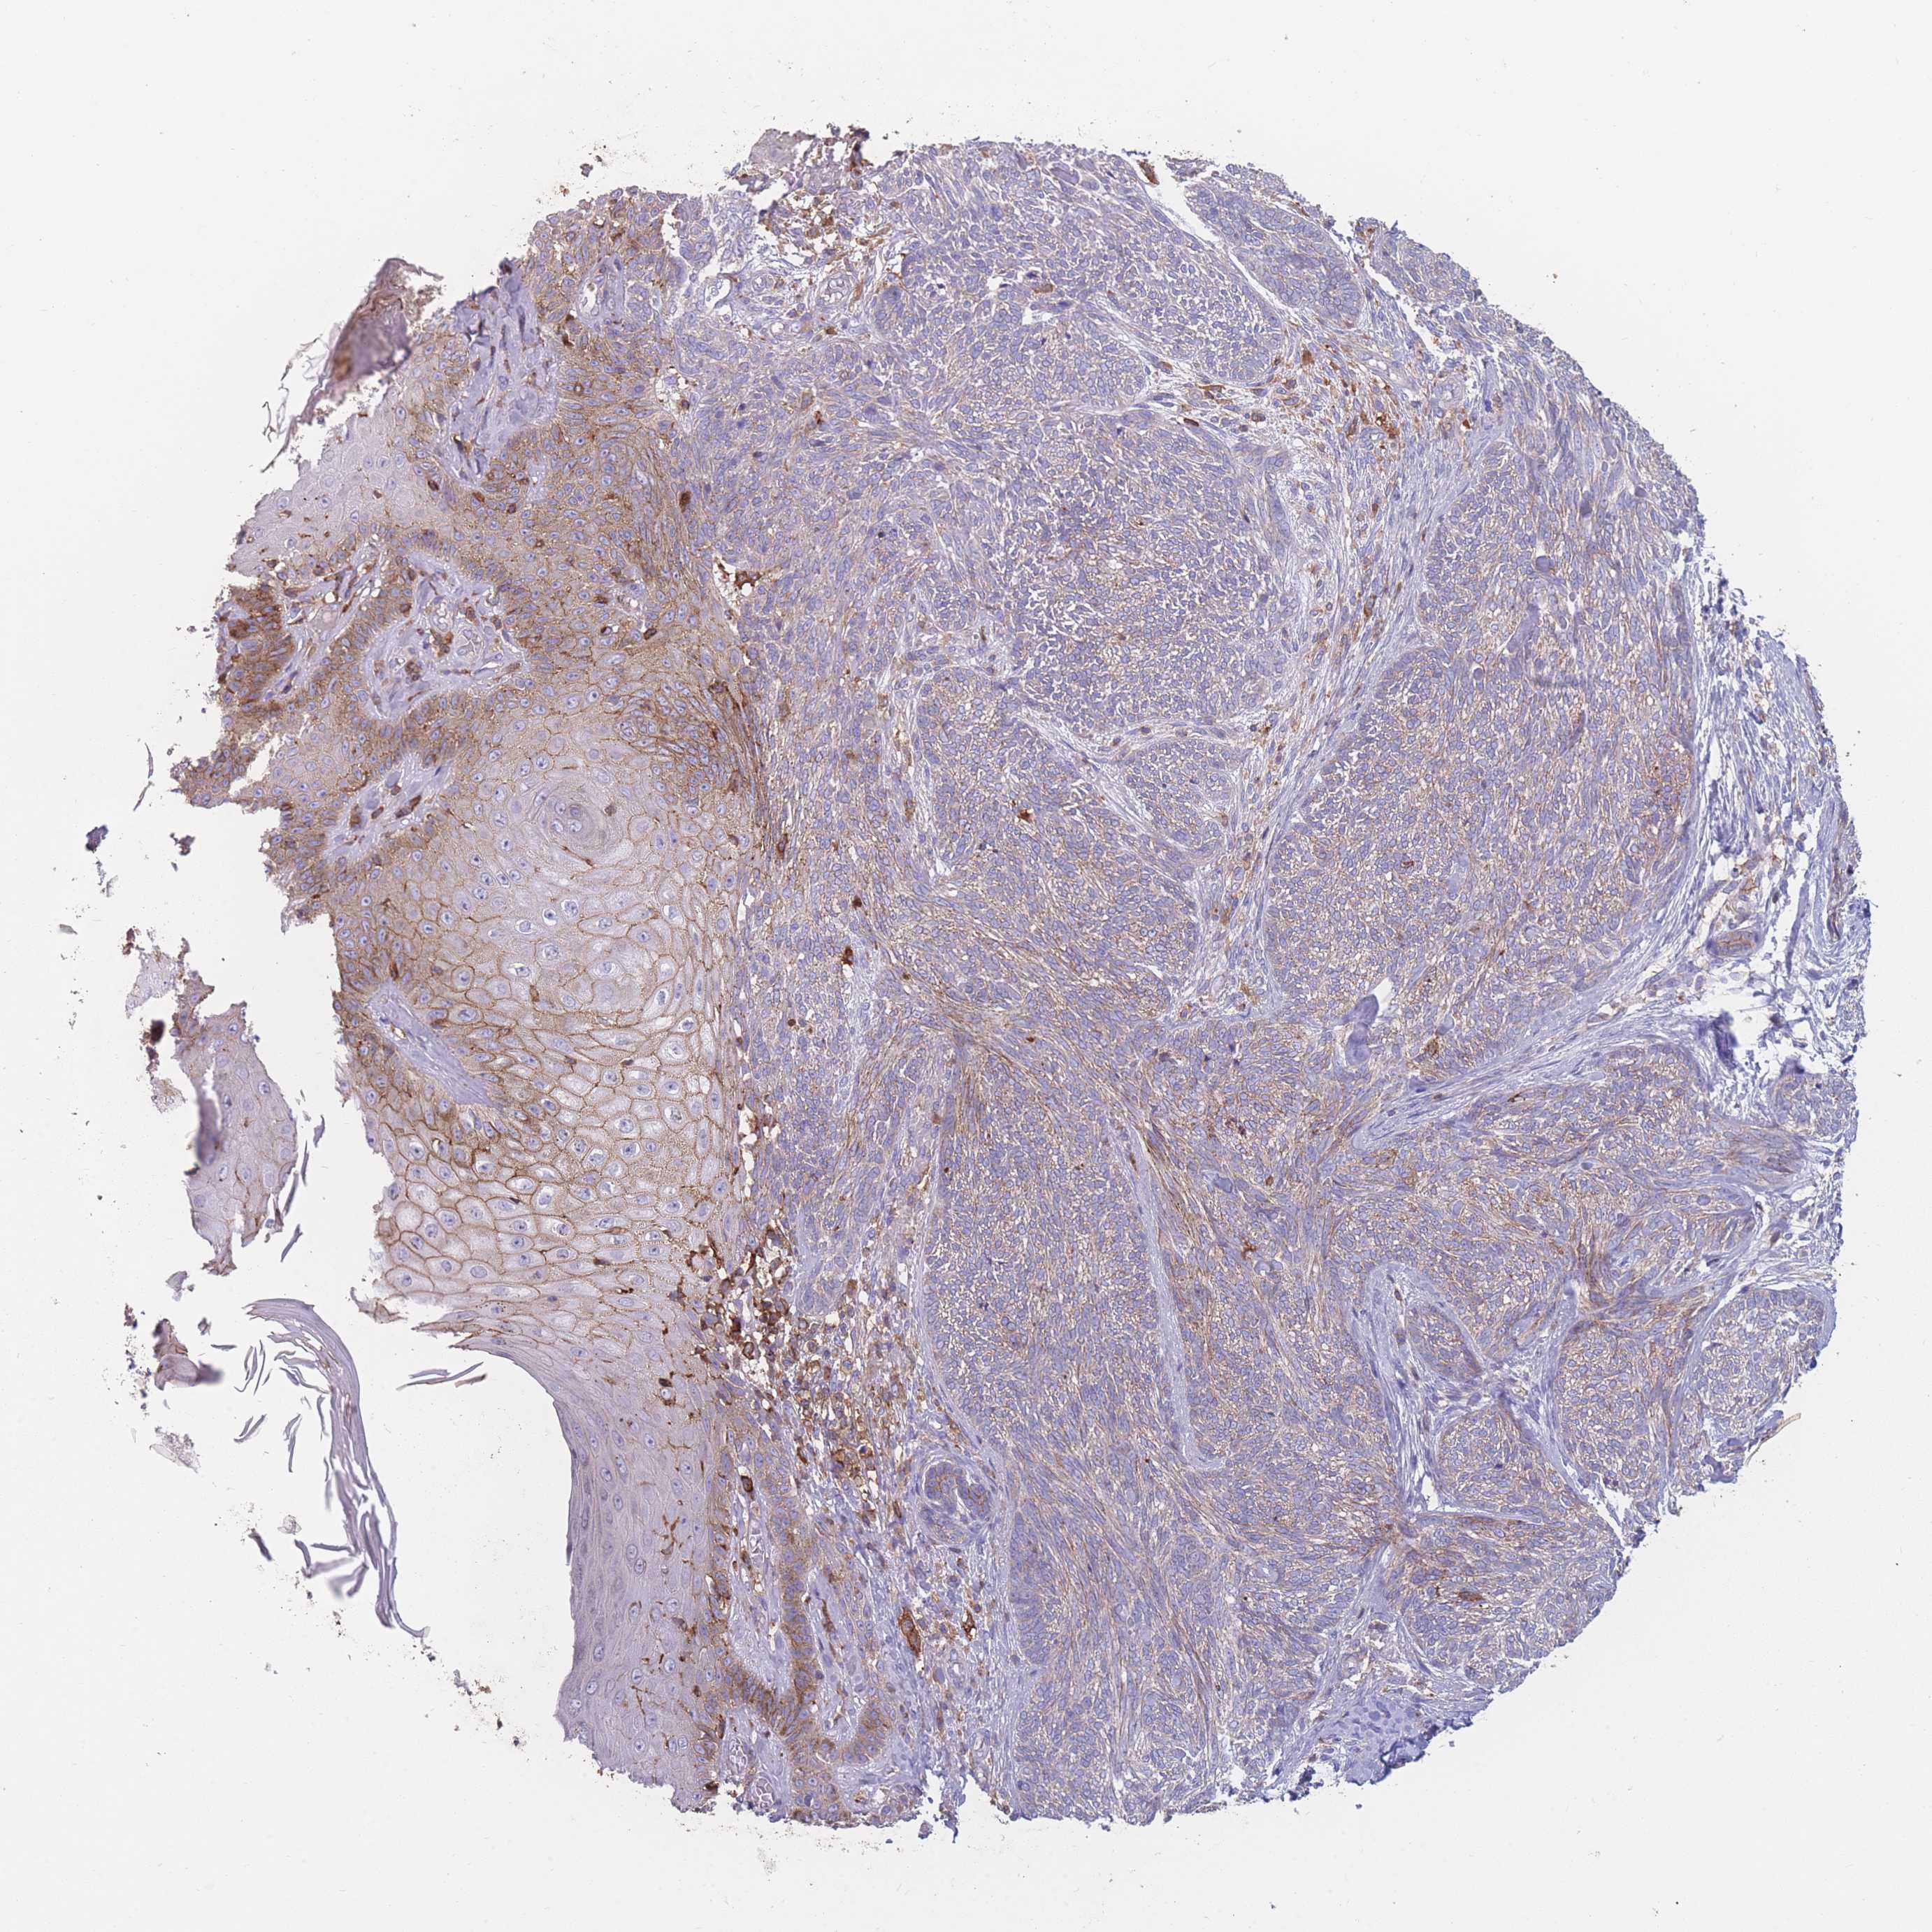

Basal cell and squamous cell cancer

SKIN CANCER - Protein expressioni

A mouse-over function shows sample information and annotation data. Click on an image to view it in a full screen mode. Samples can be filtered based on level of antibody staining by selecting one or several of the following categories: high, medium, low and not detected. The assay and annotation is described here.

Antibody stainingi

Antibody staining in the annotated cell types in the current human tissue is reported as not detected, low, medium, or high, based on conventional immunohistochemistry profiling in selected tissues. This score is based on the combination of the staining intensity and fraction of stained cells.

Each image is clickable and will lead to virtual microscopy that enables deeper exploration of all samples and also displays staining intensity scores, fraction scores and subcellular localization as well as patient and tissue information for each sample.

Antibody CAB079996

Basal cell carcinoma

Squamous cell carcinoma, NOS

Squamous cell carcinoma, metastatic, NOS

Papilloma, NOS